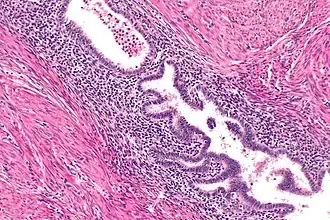

Gallbladder adenomyomatosis is a benign disease of the gallbladder characterized by hyperplasia of the mucosal epithelium and smooth muscle cells inside the muscularis propria.[4][5][6] The excessive proliferation of epithelial cells causes the mucosa to invaginate into the muscular layer lining the gallbladder wall, resulting in characteristic diverticula known as Rokitansky-Aschoff sinuses. These sinuses may be filled with biliary sludge, cholesterol crystals, or gallstones.[4][5][6]

There are three morphologic variants described in the literature – diffuse, segmental, and localized.[5][6] Diffuse, also known as generalized, adenomyomatosis has a widespread distribution of hyperplastic changes and thickening across the gallbladder wall.[5][6] The localized form of adenomyomatosis is also known as a gallbladder adenomyoma (in a similar manner that uterine adenomyoma is the localized variant of adenomyosis). The localized form is a single mass, typically in the fundus, that protrudes into the lumen of the gallbladder in the form of a polyp.[5][6] The segmental form is characterized by its annular (ring-shaped) distribution of adenomyomatosis in the body of the gallbladder, often giving it an hourglass-like appearance.[5][6]

Ultrasound is the preferred initial diagnostic choice for suspected gallbladder disease. Several distinct features of adenomyomatosis are discernable using ultrasound, making it a reliable modality for diagnosis.[4][5][6] The most characteristic features seen on ultrasound are the Rokitansky-Aschoff sinuses, which present either as echogenic foci when filled with biliary sludge/gallstones or anechogenic foci when filled with normal bile.[4][5][6] Other key features that may be seen include wall thickening and ring-down artifacts known as "comet tails" (produced by reverberations of sound between the sinuses).[4][5][6] Ultrasound can also distinguish between diffuse, segmental, and localized variants of adenomyomatosis based on morphology.[5][6]

In some cases, gallbladder wall thickening may be seen on ultrasound but is poorly defined and lacking specificity, particularly if the characteristic Rokitansky-Aschoff sinuses are not visualized. This can make it difficult to distinguish adenomyomatosis from other conditions that result in gallbladder wall thickening such as gallbladder cancer.[4][5][6] In these cases, MRI can prove helpful in providing the resolution needed for diagnosis. Especially effective is the T2-weighted MRI at visualizing the pathognomonic Rokitansky-Aschoff sinuses, which appear as round-shaped hyperintense cystic spaces that align in a curvilinear fashion along the gallbladder wall in a pattern described as the ”pearl necklace sign”.[4][5][6]